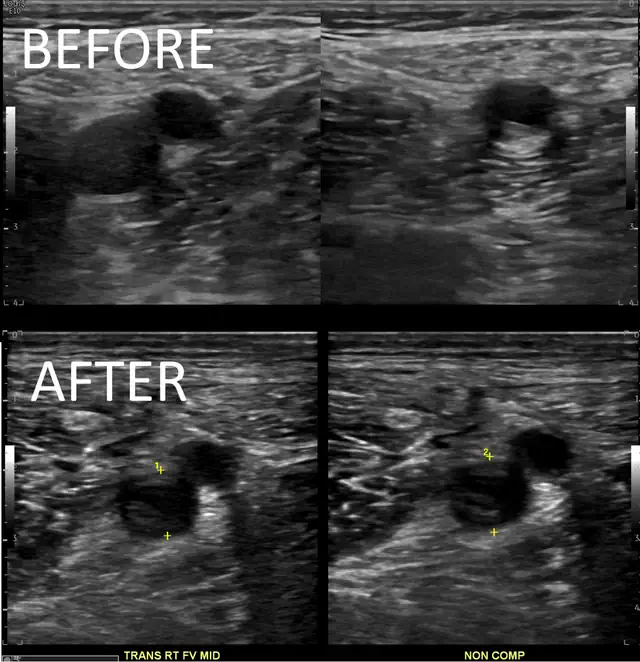

It is important to know that it can be hard to know if a person has acute or chronic clot. But in some people we can prove that there is more new clot. For instance, the DVT extended compared to a previous ultrasound. Or, there are new PE in a location where there were none before. If that happens, we call it anticoagulation failure.